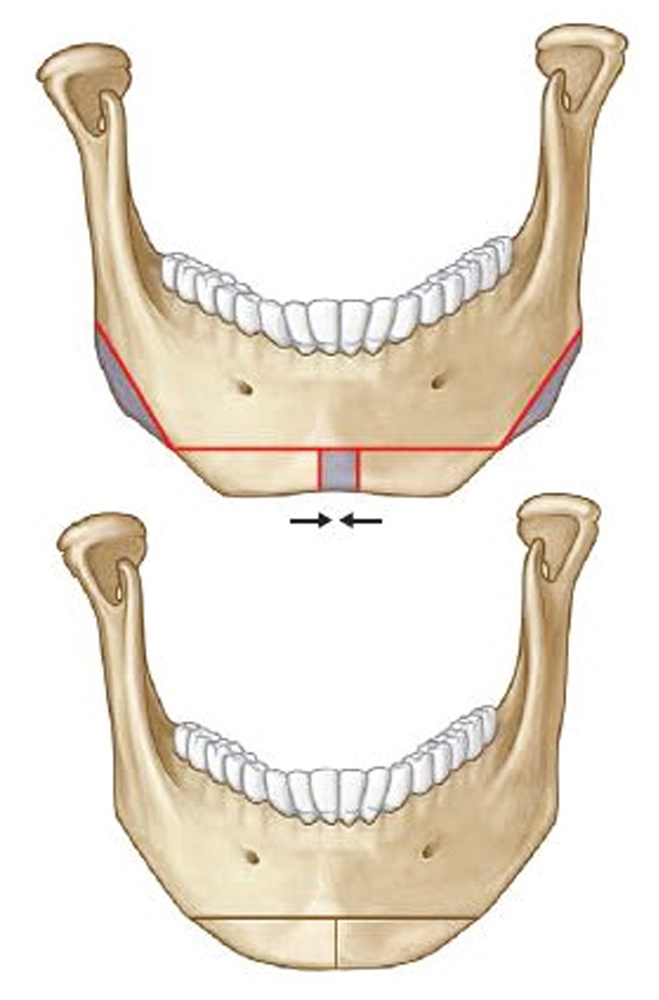

Similarly, the traditional mandibuloplasty, known as “mandible reduction” or “mandible angle reduction,” has evolved. In the 1990s and early 2000s, most Asian plastic surgeons focused on mandibular angle reduction to reshape the mandibular angle. As the concept of addressing the entire mandible evolved, treatment was no longer limited to the angle, and techniques involving the entire mandible were developed. Today, contemporary mandibuloplasty involves addressing all of the components of the mandible, not only the mandibular angle but also the body and the chin. Although simple mandibular angle reduction did improve the posterior width of the facial contour, patients noticed the residual and unintended consequences of a wider contour of the chin following mandibular angle reduction. As a consequence, contemporary mandibuloplasty must be individualized and address the aesthetic goals of the entire mandible in three dimensions and not just in the single dimension of the mandibular width. Today, we place a greater emphasis on position and the 3D shape of the chin. For the Asian ideal, we have found that the use of narrowing genioplasty or chin contouring is effective for shaping the patient’s facial contour ( Fig. 23.2 ). By combining contemporary malarplasty and mandibuloplasty as simultaneous procedures, the surgeon has the ability to reshape the upper and lower thirds of the face ( Fig. 23.3 ).

Genioplasty in Asian patients, either for reduction or advancement, is a procedure similar to that performed in Caucasian patients. The most common procedure in Asian women is narrowing genioplasty to make the lower face appear slender and the chin appear more feminine. This procedure is appropriate for the trapezoid, or broad chin, morphology.